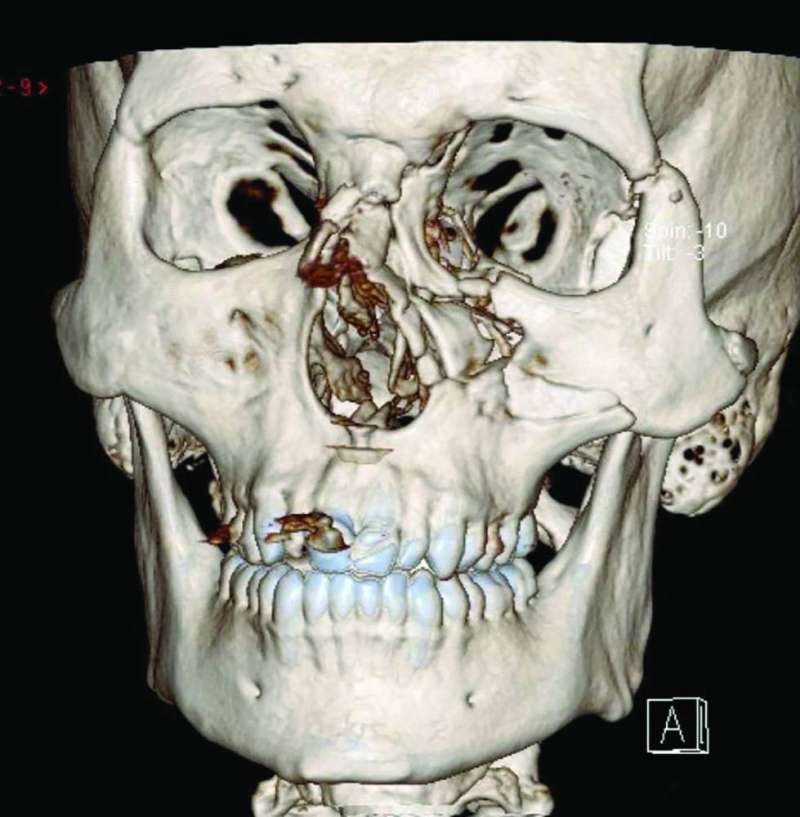

وأوضح الدكتور السجان، في تصريح صحافي، أن كسور قاع العين تعتبر ثالث الكسور في الوجه من حيث الترتيب وهي دلالة على أنها إشاعة نسبياً عند التعرض لكدمات الوجه، لافتاً إلى أن تشريح قاع العين يشمل سبعة عظام تتحد معاً لتشكل تجويف العين أو الحجاج وهو عبارة عن تجويف عظمي من هذه العظام السبعة يحوي مقلة العين والأوعية الدموية والأعصاب والعضلات.

وأكد أن الاشتباه في وجود كسر في الوجه يستلزم إجراء أشعة مقطعية مع عدم نفخ الأنف، لمنع دخول الهواء إلى الشق الكسري، مبيناً أن من بين أهم وأبرز الأعراض السريرية عند وجود كسر في قاع العين قد يكون هناك ازدواجية في الرؤية وإعاقة في حركة مقلة العين يصاحبه أحياناً تنميل في الوجه وفي أسوأ الحالات، كما قد يكون هناك غور في مقلة العين نتيجة هبوط العضلات في الشق الكسري ونزول الأنسجة الرخوية إلى جوف الجيب الفكي.

وأوضح أن إصلاح كسور قاع العين باستخدام جراحات مناظير الجيوب الأنفية هي تقنية جراحية تجميلية جديدة الهدف منها استعادة أفضل وظيفة فسيولوجية ممكنة مع إعطاء المريض مظهراً جمالياً دون الحاجة لإصلاح الكسر عن طريق فتح الجلد الخارجي وما ينتج عنه من تشوهات في شكل الوجه وهالة من آثار نفسية سيئة على المريض.

وأشار إلى أن استخدام المناظير يوفر للجراح رؤية بصرية واضحة مع سهولة في الوصول لقاع العين المكسور عن طريق الجيب الأنفي الفكي، مما يترتب عليه ترميم الكسور مع وضع شريحة لمنع هبوط الأنسجة الرخوية إلى الجيب الأنفي وتحرير العضلات العالقة داخل الشق الكسري.